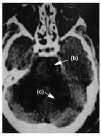

Figura 3.

En la figura 1 se aprecia hipodensidad en la región protuberancial izquierda y en hemisferios cerebelosos que comprimen la parte posterior de la cisterna protuberancial. En la figura 2 se observa una hiperdensidad en la salida de la arteria cerebral media (ACM) derecha (a) e hipodensidad de su territorio tributario, y en la figura 3 una hipodensidad de todo el territorio de la ACM derecha. Las flechas de la imagen delimitan la zona isquémica y señalan la hiperdensidad de la ACM, posición M1.

Diagnóstico: infarto de la protuberancia (b), cerebeloso (c) y del territorio de la ACM derecha (d) con visualización de la oclusión de la arteria tributaria de origen embólico.